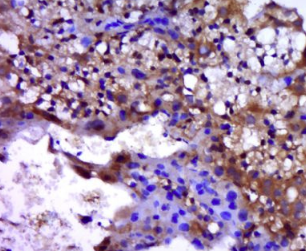

多聚甲醛固定,石蜡包埋(小鼠胎盘组织);用柠檬酸钠缓冲液(pH6.0)煮沸15min后获得抗原;用3%过氧化氢阻断内源过氧化物酶20分钟;阻断缓冲液(正常山羊血清)37℃30min;用β细胞培养液进行抗体孵育nin)未结合的多克隆抗体在1:400下在4°C下过夜,然后结合二级20分钟,DAB染色。